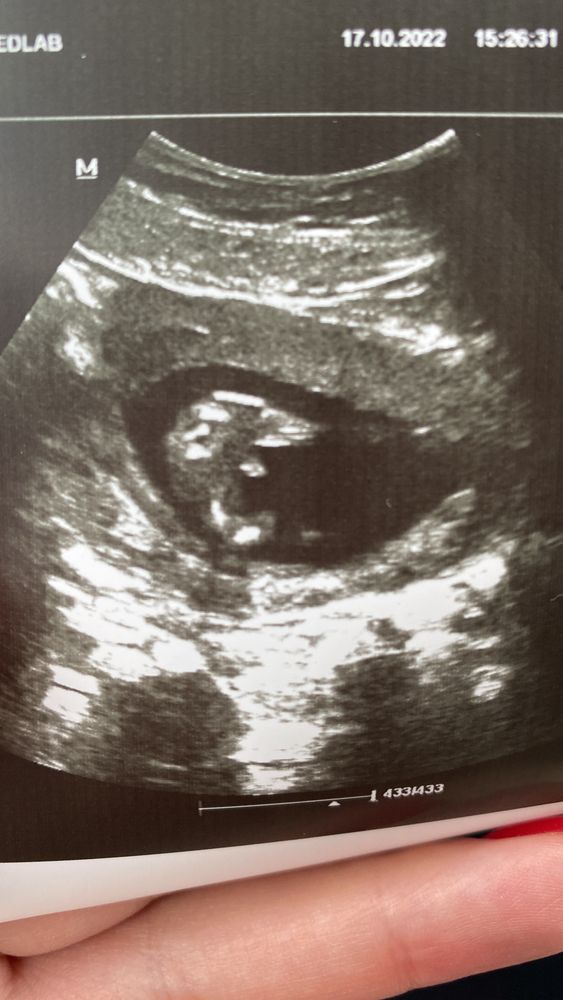

Точно мальчишка))) вот мое узи, я делала Нипт поэтому и без узи знала) Изображение

MissKanaverel, у вас прям так четенько видно) девочки предполагают, что может быть пуповина, но на экране, когда в конце показывали малыша, даже крупнее все мальчишечьи дела увидела))